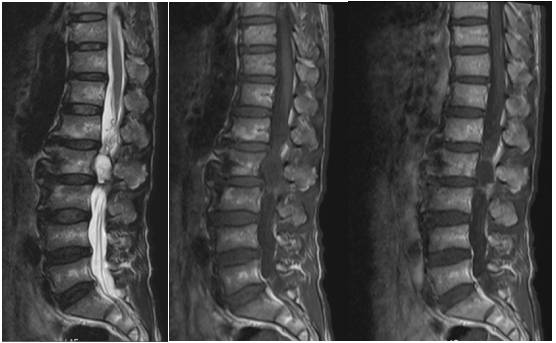

入院后查腰椎CT及腰椎增强MRI(图1)、(图2)。显示占位位于腰2椎体水平左侧腰1/2关节突内侧硬膜外,诊断首先考虑关节滑膜囊肿,囊性神经鞘瘤可能性较小。科室讨论,根据病灶位置及性质,拟行经皮脊柱内镜下探查,明确病灶性质,若术中探明属神经鞘瘤也可转显微开放手术。完善必要检查,与患者及家属沟通,知情同意后行脊柱内镜下经椎板间入路椎管探查+囊肿切除术。

图1. 腰椎增强MRI,腰2椎体水平椎管内占位,大小约18.8mmx16.9mmx30mm(左右x前后x上下)。病灶病灶类圆形,边界清晰,位于椎管左侧膜外间隙,边缘紧贴黄韧带,硬膜囊向右侧推压,相应马尾神经推压。病变上方马尾神经冗余、紊乱,提示椎管狭窄和神经受压。椎间孔未见扩大,邻近椎体后缘轻度受压吸收。T1和T2加权图像,病变核心液性信号,周边囊壁低信号。增强扫描,囊壁强化明显。